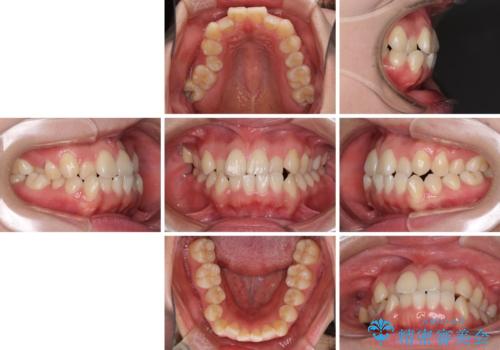

- 前歯のデコボコとクロスバイトを気にして来院された患者様です。

骨格的に下顎が前方位の受け口傾向であり、それが原因でクロスバイトとなっていました。

受け口傾向の非抜歯矯正であったため、インビザラインによる矯正治療をお勧めしましたが、自己管理が面倒であるとのことで、ワイヤー装置にて行うこととしました。

なお、右奥の歯が180度回転した状態で萌出しており、こちらは改善困難なため、そのままの向きで配列することとしました。